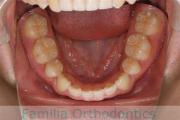

- ≫治療前

-

上顎

下顎

- ≫治療後